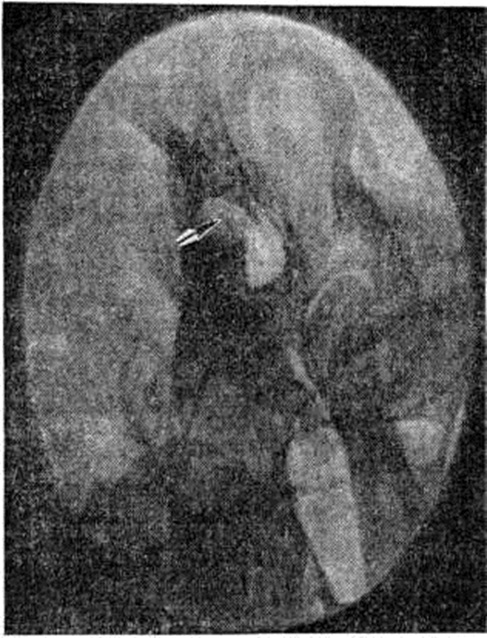

Важное диагностическое значение в сочетании с клинические, данными имеет рентгенологическое исследование. Рентгенографию височной кости производят в специальных проекциях (смотри полный свод знаний: Среднее ухо). Ценные дополнительные сведения могут быть получены при томографии височных костей в прямой и боковой проекциях (смотри полный свод знаний: Краниография). Рентгенологические картина зависит от размеров и локализации холестеатомы уха, которая распознается по вторичным признакам — изменениям в прилежащих костных структурах. Небольшие холестеатомы могут не давать рентгенологическое симптоматики. Крупная холестеатома приводит к увеличению размеров сосцевидной пещеры и надбарабанного углубления, истончению и разрушению наружной стенки последнего и входа в сосцевидную пещеру. Контуры дефекта кости, образованного неосложнённой холестеатомой, чёткие, дефект имеет округлую или полигональную форму с небольшой склеротической полоской по периферии (рисунок). Отсутствие чёткой и плотной капсулы холестеатомы является рентгенологическим признаком обострения процесса.

Рис.

Рентгенограмма пирамиды левой височной кости больного холестеатомой уха (в проекции по Майеру): стрелкой указан овальной формы дефект в области надбарабанного углубления со склеротическими изменениями по периферии, обусловленный холестеатомой.